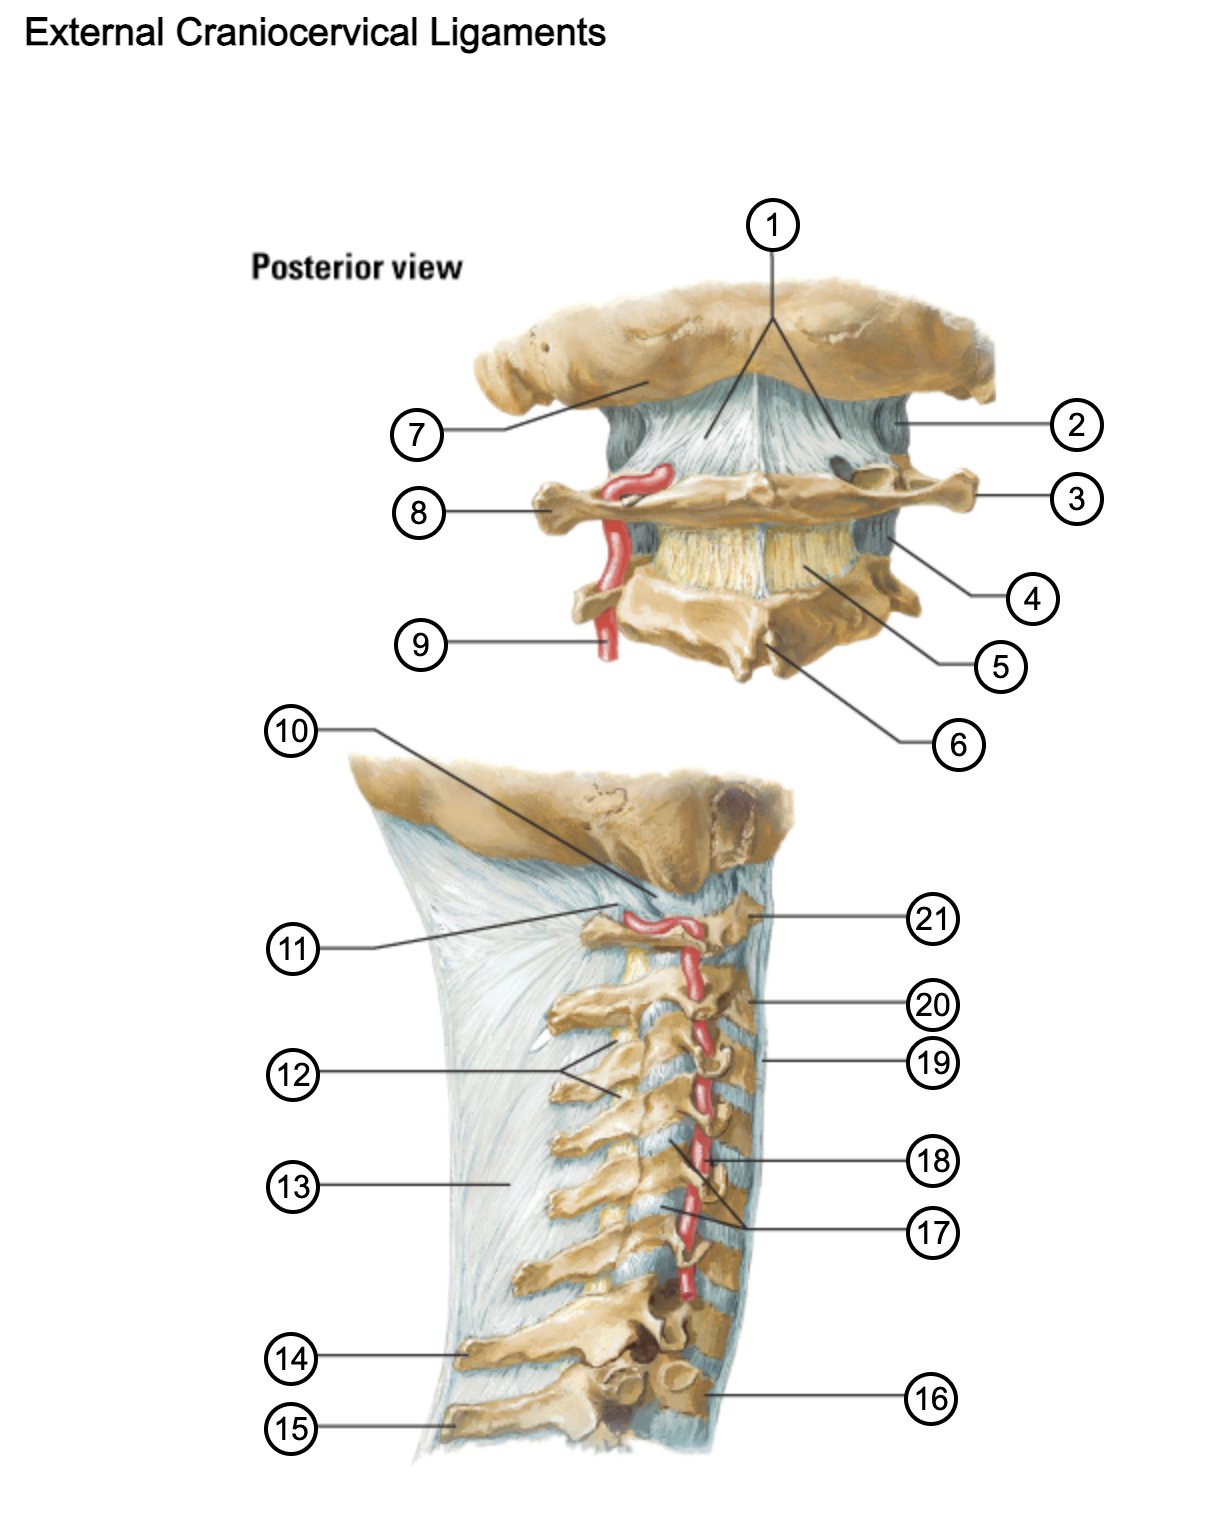

1

posterior antlantooccipital membrane

2

capsule of atlantooccipital joint

3

transverse process of atlas (C1)

4

capsule of lateral atlantoaxial joint

5

ligamenta flava

6

spinous process

7

occipital bone

8

transverse process of atlas (C1)

9

vertebral artery

10

capsule of atlantooccipital membrane

11

posterior atlantooccipital membrane

12

ligamenta flava

13

nuchal ligament

14

spinous process of C7 vertebra

15

spinous process of T1 vertebra

16

T1 vertebra

17

zygapophysical joints (C4-5 and C5-6)

18

vertebral artery

19

anterior longitudinal ligament

20

body of axis

21

Atlas (C1)